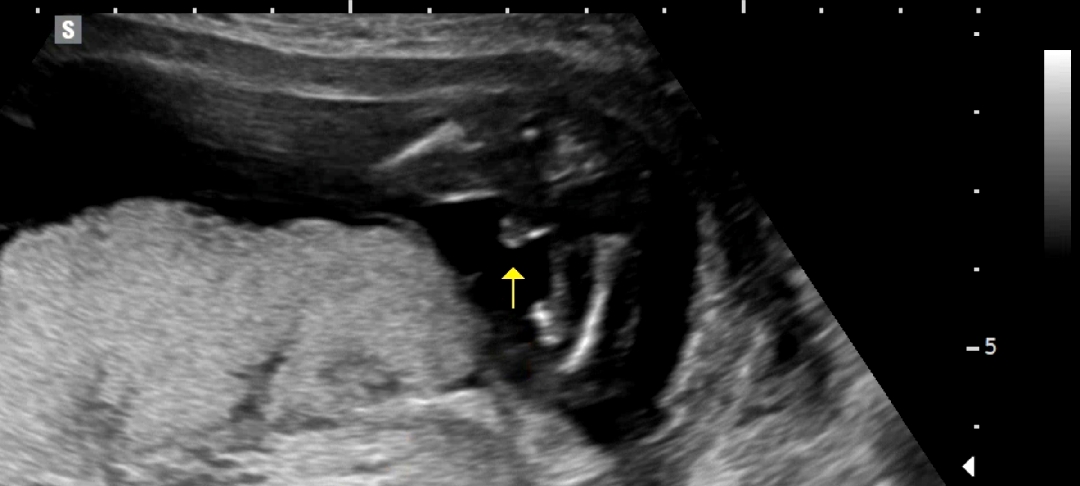

16개월 아들맘 입니다.^^ 오늘 둘째 16주 초음파 봤는데, 다리 사이에 보이는게 있다며 아들 가능성이 높다고 하시네요^^ 아들이든 딸이든 건강하게만 태어나주길 바라는데, 주변에서 많은 분들이 딸이면 좋겠다고 너무 그래서.. 아들이라고 했을때 어떤 반응일지 마음이 좀 그렇네요..ㅜㅜ 정작 저하고 남편은 큰 상관 없는데 말이죠..^^ 그냥 아들 딸 상관없이 건강하길 바란다고 말해주면 참 감사할 것 같아요^^ 지금 첫째도 너무 예뻐서.. 둘째도 너무 예쁠것 같아요♡ 아들맘 딸맘 모두모두 파이팅 입니다.!!